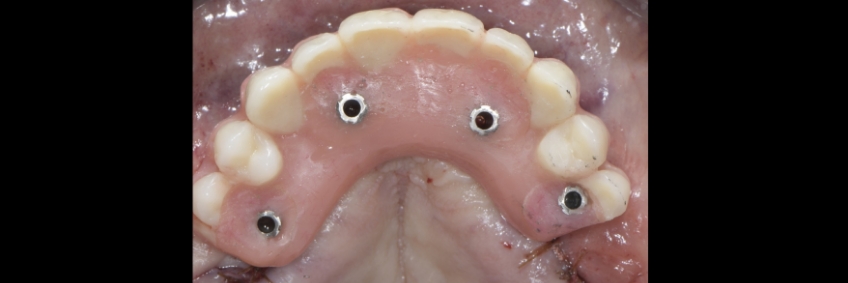

Usually, straight SRA abutments are used with anterior implants when they are parallel. Still, it is not uncommon for the restorative dentist to realize during the prosthetic phase of treatment that the position of the screw access hole could be optimized by changing the angulation of the SRA abutments. Ideally, the treating team aims to have the access holes coming out of the cingulum in anterior implants and the center of the occlusal area in posterior implants.

This visual essay shows, through a series of images, the fabrication of a maxillary implant-supported fixed dental prosthesis. The SRA abutments of the anterior implants were changed to optimize the definitive implant-supported fixed dental prosthesis design.

Suppose we decide to alter the angulation of the SRA abutments. In that case, we can position the access hole more anteriorly, thus increasing the palatal thickness and improving the biomechanics and hygiene access.